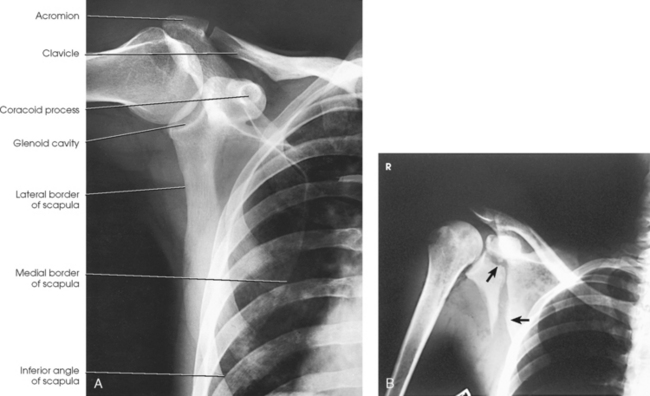

Structures shown: The image shows the bony and soft structures of the shoulder and proximal humerus in the anatomic position (Figs. 5-14 to 5-16). The scapulohumeral joint relationship is seen.

Fig. 5-14 A, AP shoulder, external rotation humerus: greater tubercle in profile (arrow). B, AP shoulder, neutral rotation humerus: greater tubercle (arrow).

Fig. 5-15 AP shoulder, internal rotation humerus: greater tubercle (arrow); lesser tubercle in profile (arrowhead).

Fig. 5-16 A, AP oblique projection of right shoulder without use of compensating filter. B, AP projection of same patient with compensating filter. Note improvement of visualization of bony and soft tissue areas with filter.

External rotation: The greater tubercle of the humerus and the site of insertion of the supraspinatus tendon are visualized (see Fig. 5-14, A).

Neutral rotation: The posterior part of the supraspinatus insertion, which sometimes profiles small calcific deposits not otherwise visualized (see Fig. 5-14, B), is seen.

Internal rotation: The proximal humerus is seen in a true lateral position. When the arm can be abducted enough to clear the lesser tubercle of the head of the scapula, a profile image of the site of the insertion of the subscapular tendon is seen (see Fig. 5-15).